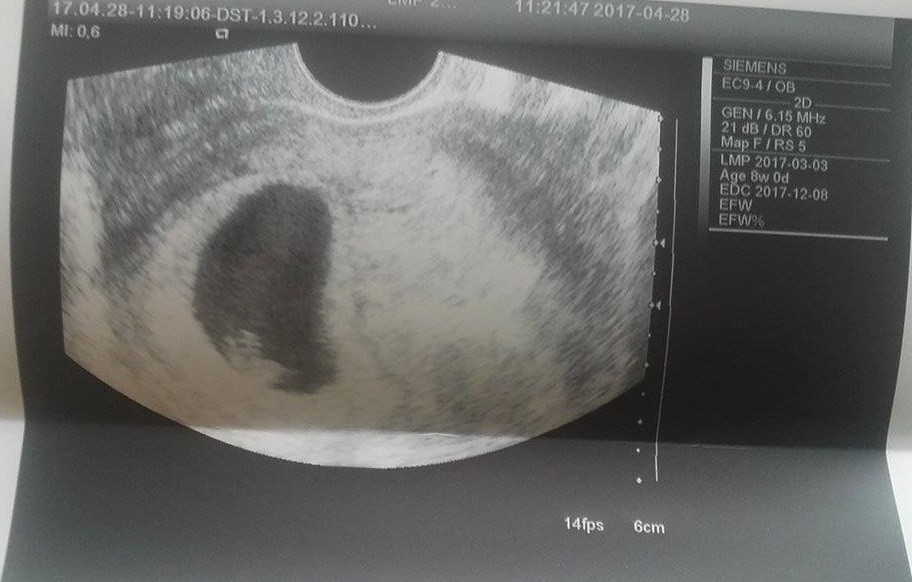

A to jest nasz Dziedzic :)

Hej, była obsuwa, właśnie skończyłam wizytę. Chyba zaraz latać zacznę :) Maleństwo sporo urosło i jak wcześniej było o 3 dni młodsze niż wg OM, to teraz o 1 dzień starsze, czyli 8t1d ;) Widziałam i słyszałam serduszko, yupii. Tylko lekarz mi nie dał zdjęć :( ale za to pozwolił cyknąć fotkę jak bardzo poprosiłam. Teraz termin mi się przesunął na 8.12 ciekawe jak to ostatecznie będzie... Sorki że tak chaotycznie ale cała w skowronkach jestem, kolejna wizyta 17.05, a do tego czasu reszta badań.

Zobacz załącznik 804346 Zobacz załącznik 804347 Zobacz załącznik 804348